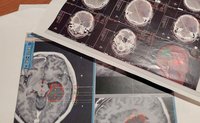

何十回も受けたMRIの画像